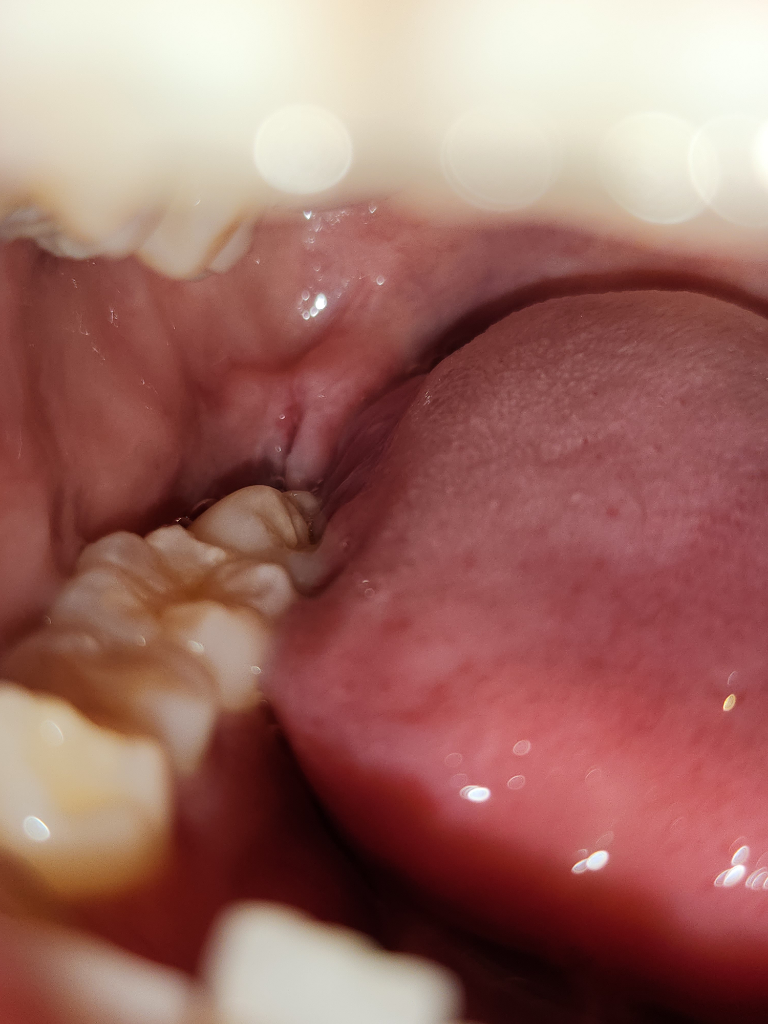

사진으로 보아 잘 아물고 있습니다. 이제 겨우 1주일 지나고 실밥 뽑은 상태입니다. 아직까지 건드리면 아프고 피가 납니다. 시간이 지나면 점점 좋아지며 대개 몇달이 지나야 됩니다.

시간이 지나면 잇몸도 다 차오르고 정상 모양으로 회복됩니다. 잘 아물고 있습니다. 괜찮습니다.

사진으로 봤을경우에는 큰 문제는 없어보입니다 발치한 부위의 불편감은 시간이 지나면서 대부분 줄어듭니다